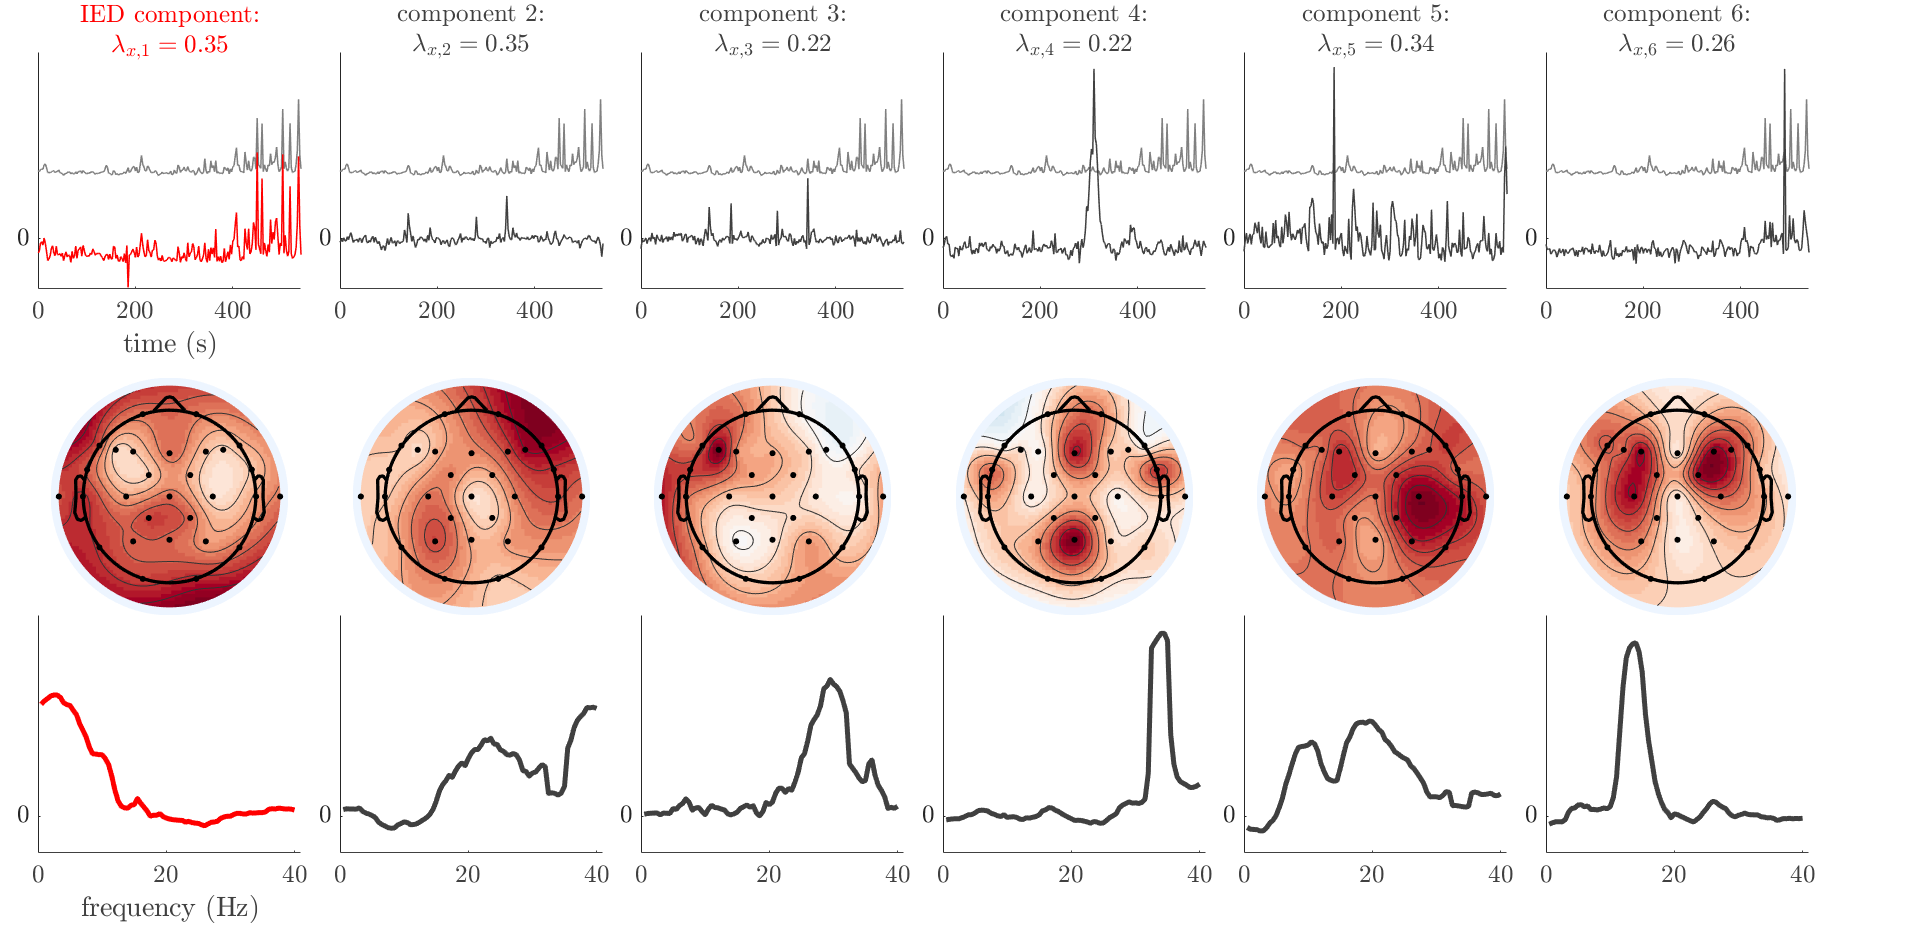

Patient 1

We analyze the solution with sources. Figure 1 shows the EEG signatures and HRF waveforms. One of the sources is highly correlated to the MWF reference (in grey), which was already known from Table B.3. This IED-related source had a typical low-frequency spectrum, which is expected for the typical spike-and-wave interictal discharges. The topography is relatively diffuse, although the highest amplitudes are mostly in the left hemisphere. This is in accordance with the lateralization of ictal onset zone (left temporal lobe, cfr. Table 1). There are some noteworthy observations to be made about some of the other components. The fourth has an unusually sharp spectrum, is mainly localized on two nonadjacent center electrodes, and is sustained for a single period of many seconds Hence, this component likely captured an artifact (of yet unknown origin), although we spotted no large-amplitude changes in the EEG itself. Similarly, the third source is only present at one frontal electrode, and exists in a frequency range above 20 Hz. It might represent a muscle artifact, e.g., due to frowning or twitching of some muscles in the forehead. The HRFs of all ROIs are shown in Figure 1(b). Two of the basis functions seem to have converged to a very similar waveform, which is an unfortunate possibility if two initial HRFs are too close to the same local optimum in their respective parameters. This reduces the expressive power of the basis set, which is clearly visible, since many ROIs have a nearly identical HRF. One of the twenty ROIs with the highest-entropy HRF overlapped the IOZ, although clearly this HRF (bold line) is not among the most dissimilar waveforms for this patient. This is also visible in Figure 2: both the HRF entropy and extremity maps show a small overlap with the delineated IOZ. Despite the good correspondence in the EEG domain, no significant (de)activation of the IED-component is found inside the IOZ.